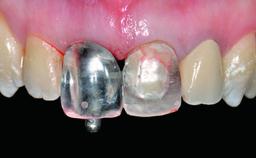

Replacement of an Ankylosed Central Incisor with a Gingival Recession: Tooth Extraction with Socket Grafting and Late Implant Placement with Simultaneous Contour Augmentation

Placement Protocol Early or late implant placement

Bone Volume Deficient vertically or deficient vertically AND horizontally